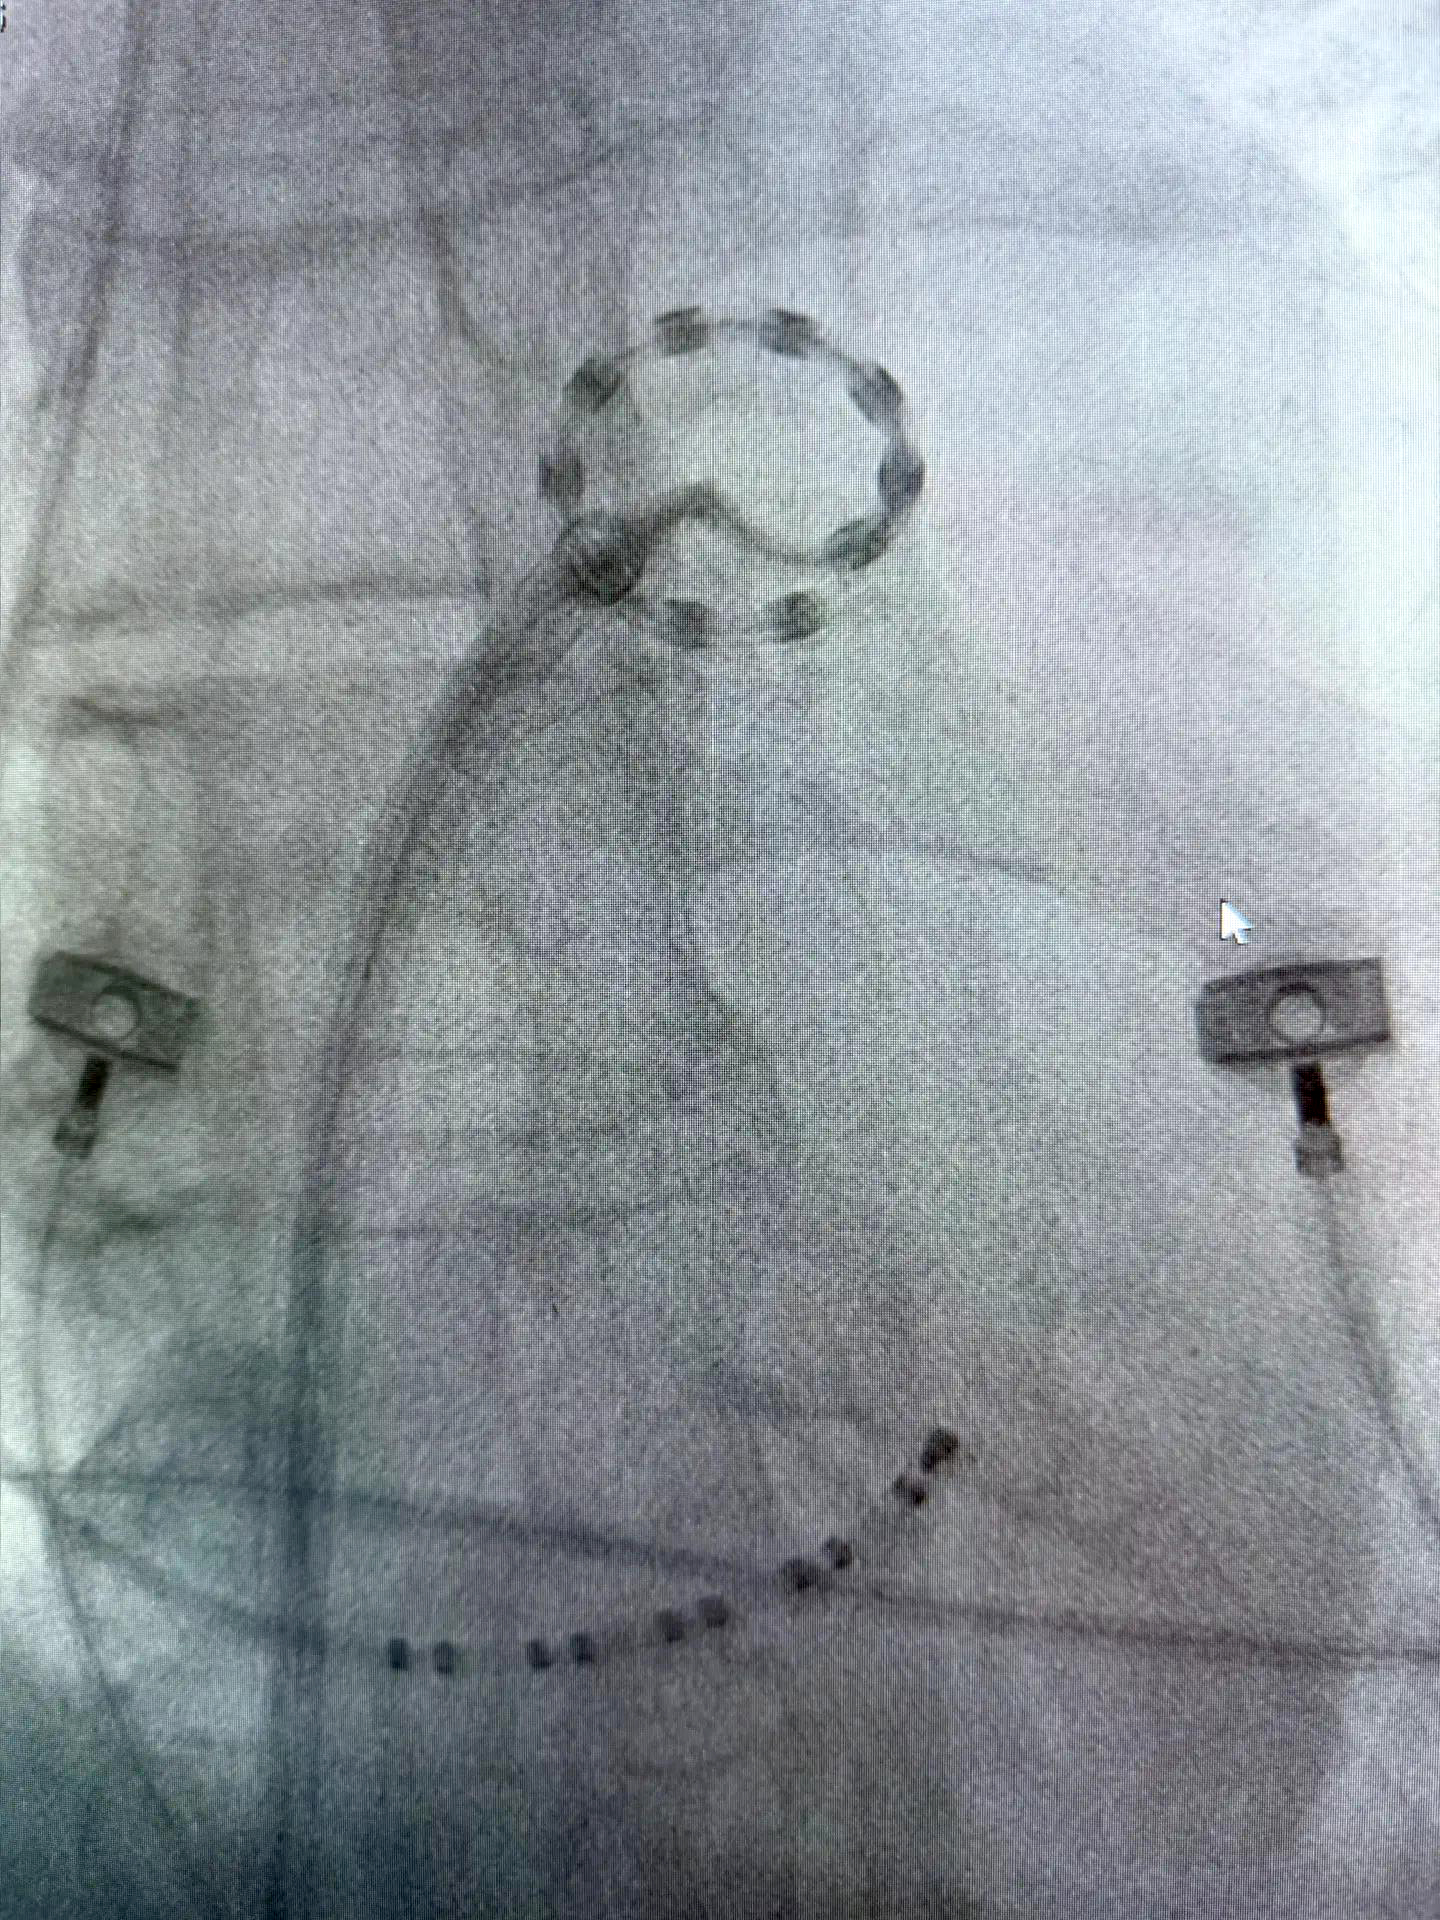

Технически это также катетерная технология, выполняется через прокол сосуда. Основной рабочий инструмент — специальный электропорационный катетер. Он имеет необычную форму, напоминающую лассо с кольцом, на котором расположены 10 миниатюрных электродов. Операция проводится под общим наркозом. Мы вводим катетер в полость сердца и последовательно устанавливаем его в устье каждой из четырех легочных вен. Воздействие представляет собой ультракороткие импульсы — это сотые и тысячные доли секунды — но с очень высокой мощностью. Через каждый электрод подается разряд, и клетки, провоцирующие патологическую активность, перестают функционировать.

«Электропорационный катетер LASSO® с 10 электродами» под рентген визуализацией